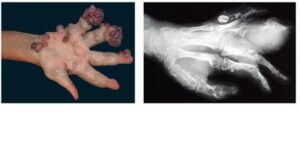

Maffucci syndrome is a rare genetic disorder that affects both males and females. Maffucci syndrome is characterized by benign enlargements of cartilage (enchondromas); bone deformities; and dark, irregularly shaped hemangiomas. No racial or sexual predilection is apparent in Maffucci syndrome. No familial pattern of inheritance has been shown, but Maffucci syndrome manifests early in life, usually around age 4-5 years, with 25% of cases being congenital. Maffucci syndrome appears to develop from mesodermal dysplasia early in life. Patients apparently are of average intelligence, and no associated mental or psychiatric abnormalities seem to be present. About 160 cases of Maffucci syndrome have been published in the English literature.1,2 Note the image below.

Maffucci syndrome affects the skin and the skeletal systems. Superficial and deep venous malformations (hemangiomas) often protrude as soft nodules or tumors usually on the distal extremities, but they can appear anywhere. The hemangiomas are usually asymmetric. Venous-lymphatic malformations can occur but are much less common. Enchondromas are benign cartilaginous tumors that can appear anywhere, but they are usually found on the phalanges and the long bones. These bone abnormalities are usually asymmetric and cause secondary fractures. Approximately 30-37% of enchondromas can develop into a chondrosarcoma.

The hemangiomas in Maffucci syndrome manifest as blue subcutaneous nodules that can be emptied by pressure. The hemangiomas can be unilateral or bilateral and are usually asymmetric. Thrombi often form within vessels and develop into phleboliths. These phleboliths appear as calcified vessels under microscopic examination.

Enchondromas develop from the mesodermal dysplasia associated with Maffucci syndrome. As the bones grow, some cartilage material is left behind and grows irregularly, developing into the characteristic bone deformities. Bone irregularities in Maffucci syndrome include shortened length of the long bones, unequal leg length, pathologic fractures, and malunion of fractures.

- Enchondromas are usually found in the hands (89%), but they can be found on, although not limited to, the foot, the tibia, the fibula, the femur, the humerus, the ribs, and the skull. The tumors appear as nodular outgrowths and can cause a fracture, leading to further complications, such as shortened or unequal length limbs. Patients who are severely affected can have difficulty walking and manually manipulating objects. Note the images below.